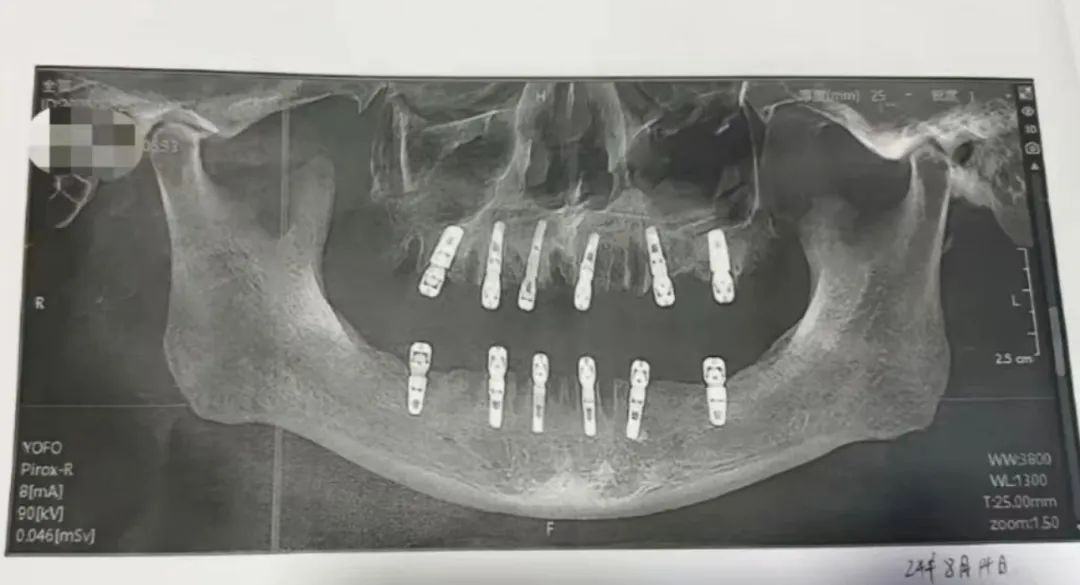

男子一天拔23颗牙种12颗,

13天后去世,

当地卫健部门已介入

近日,浙江永康市居民报料称,其父亲黄某在一家口腔医院拔除23颗牙,并种植12颗新牙,并且均为即刻修复,即“当天拔、当天种”,之后疼痛不止13天之后因心脏骤停死亡。

9月3日,永康市卫生健康局工作人员回应称:“由于拔牙和死亡时间相隔13天,黄某具体的死亡原因我们还在调查。”据口腔科医生介绍,一般来说,一次性拔除的牙齿最多在十多颗。